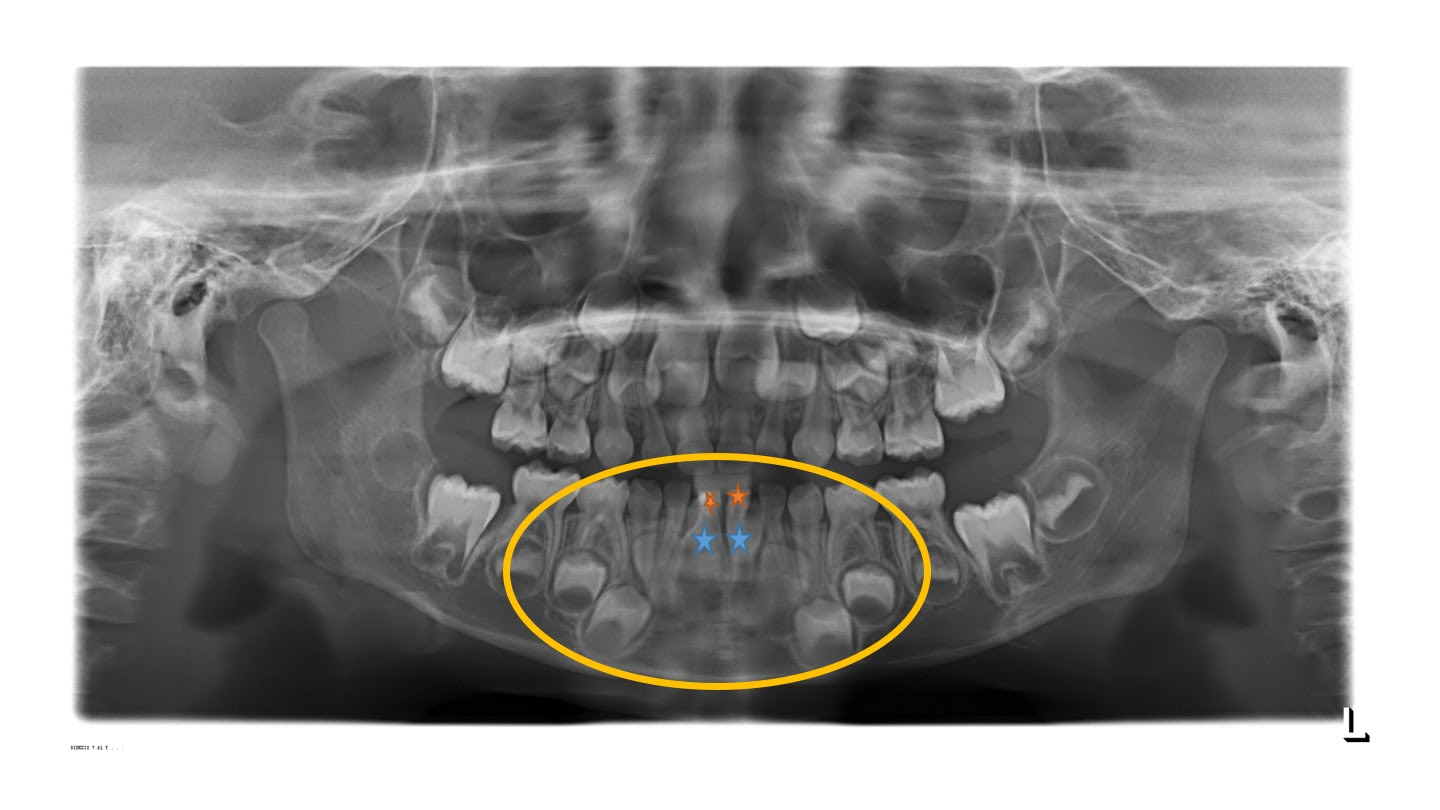

子供の矯正 叢生歯列弓 (でこぼこの歯・八重歯・乱ぐい歯)Case3 永久歯萌出期(6歳時)の来院時には治療を開始せず観察を行い、永久歯完成後に治療を開始した症例 症状 患者さん 6歳11ヶ月 男の子 主訴 下前歯のガタガタと、上前歯の正中離開。 診断 下の前歯(永久歯)が萌出中でありガタガタ12 子供の歯並び②乳歯前歯が抜ける前に永久歯前歯が生えてきた 121 乳歯前歯が揺れている場合前項目で、乳歯から永久歯に生え替わる大まかな流れを見ました。 今項目では、1年毎にその過程を見ていきたいと思います。 個人差があるため、一般的には見られる構造が見られない例もあります。 右の文字列(明るいもの)は、オンマウスで画像に反映されます。 3歳 乳歯列の完成期;

下顎のスペースが足りず 今後も歯がガタガタに生える可能性の高い症例 症例集 四街道市 あさひクリニック歯科 矯正歯科

レントゲンから獲れる情報は沢山あり どこが原因で歯茎が腫れてるかとか しっかりと交換期で歯が生え変わるか 親不知の埋伏状態 根が化膿していないか など様々です 広島市安佐南区の歯科医院